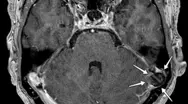

De sjældne forandringer kan ses ved en MR-scanning. Emnet er endnu ikke beskrevet i dansk litteratur, og der er ikke megen viden om det. Forandringen er sagt i enkelthed den, at en del af hjernen har dannet et “brok” ind i en normal struktur tilhørende hjernens hinder, de såkaldte arachnoide granuleringer (AG), som blandt andet ligger inkorporeret i de store venestrukturer (sinus), der leder blodet fra hjernen. AG er normalt af betydning for at lede hjernevæsken bort fra rummet omkring hjerne og rygmarv og er dermed med til at bortskaffe affaldsstoffer med mere via blodbanen.

Det lille brok ind i AG kaldes samlet set BHAG, hvilket står for Brain Herniations into Arachnoid Granulations (se billedet). Brokket kan være af forskellig størrelse, men omkring 10 mm er almindeligt. Det kræver således tynde snit og høj opløsning for at kunne se dem. De moderne skannere er netop karakteriseret ved at skanne med tyndere snit og højere opløsning, så man må forvente at se flere af dem fremadrettet.